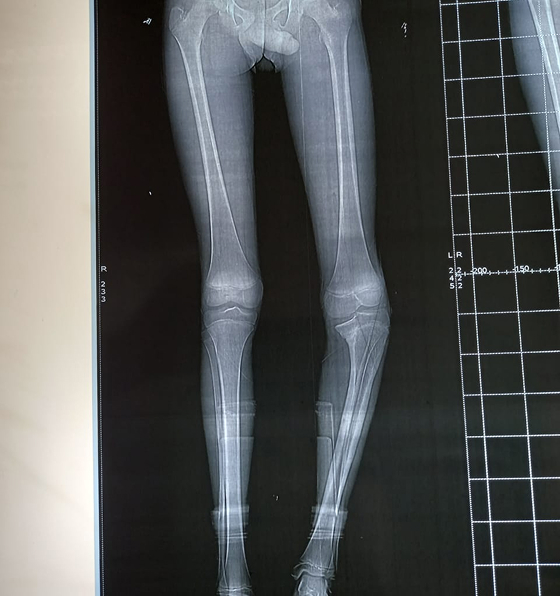

Caring for Growing Knees

Knee issues are common in children, ranging from sports injuries to growth-related alignment problems like knock-knees or bow legs. Early treatment prevents future pain and deformity.

We provide:

- Treatment for ligament injuries and meniscus tears

- Non-surgical care for alignment concerns

- Surgical correction for severe deformities

- Sports medicine for active children and teens

“From playground tumbles to sports injuries, every knee tells a story, we make sure it heals the right way.”